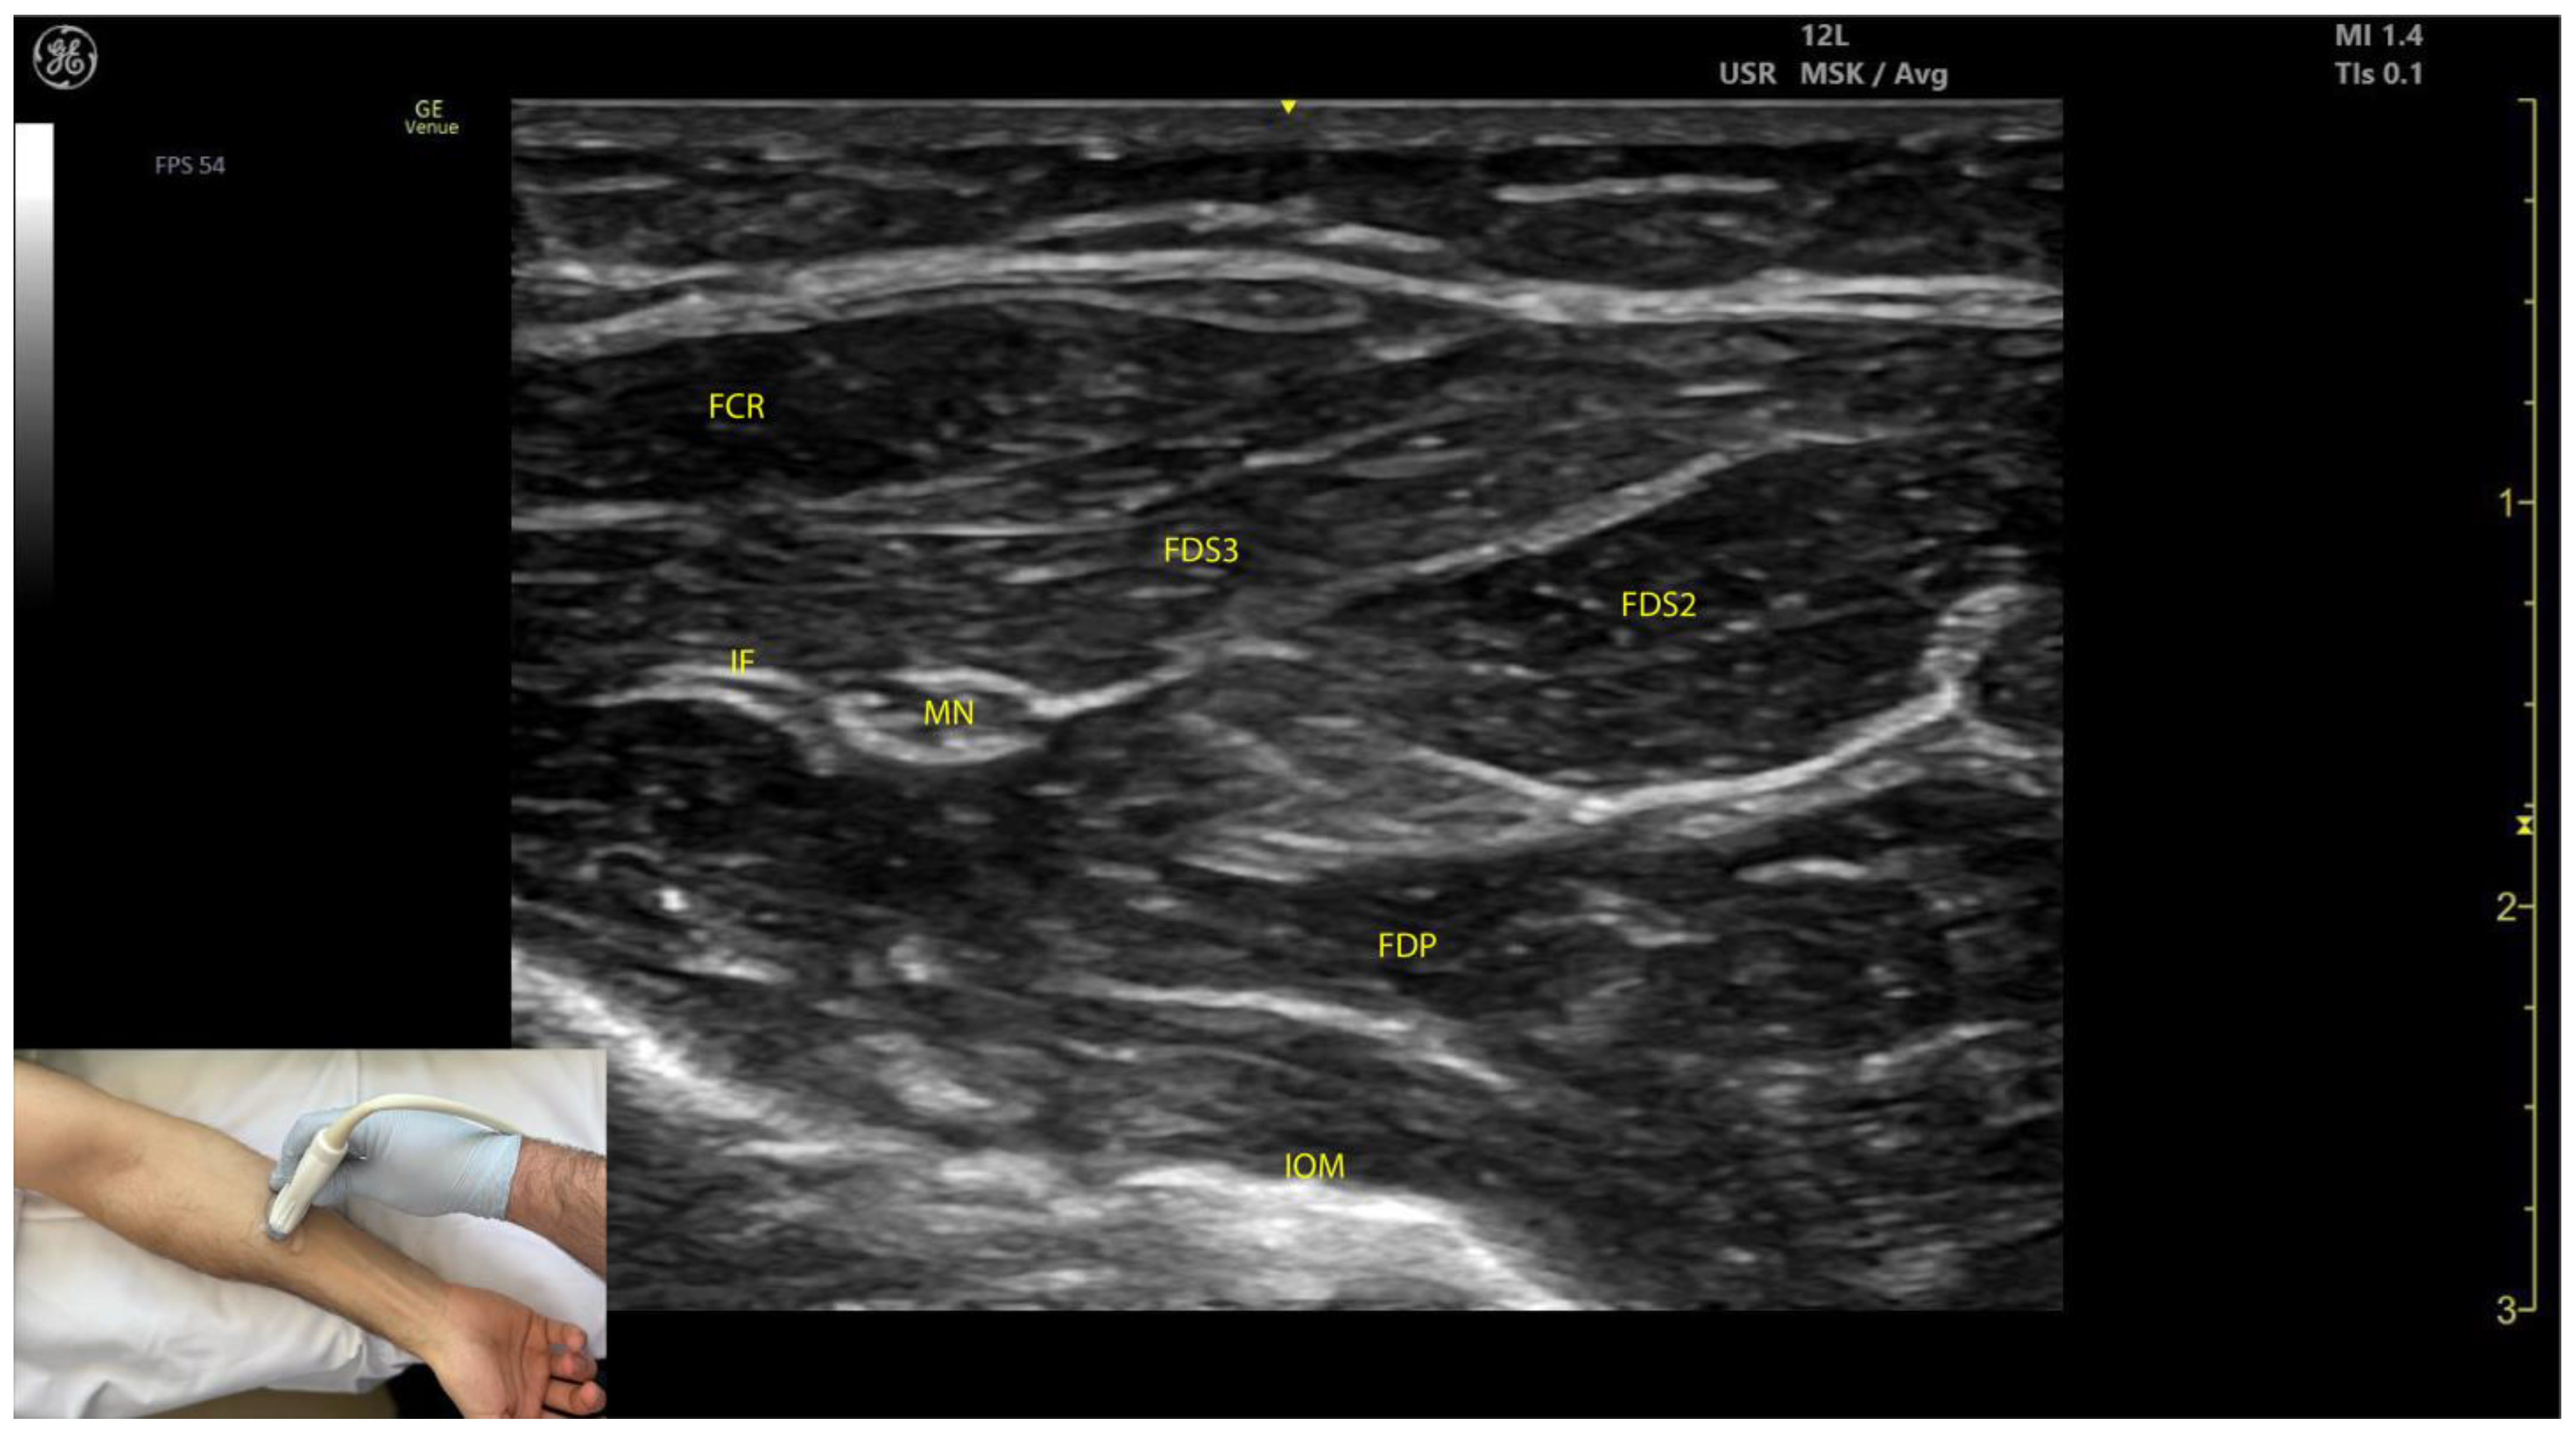

2.4.3. Key Ultrasound Landmarks (Figure 4 and Figure 5)

- Muscle position: At the mid-forearm, the FDS represents the second muscle mass from the cortical surfaces of the radius and ulna, moving from deep to superficial. Superficial to the FDS are the lateral FCR and medial FCU [29]. In the absence of US guidance, these adjacent muscles may be mistaken for the FDS, increasing the risk of injection errors.

- Median nerve: The median nerve is adhered to the deep surface of the FDS. At this level, the FDS and FDP are separated by the intermuscular fascia, which houses the median nerve, ulnar nerve, and ulnar artery [26].

- External fascia: FDS2 and FDS3 have a pronounced external fascia that distinctly demarcates them from adjacent muscle masses during BoNT-A injections, whereas FDS4 and FDS5 lack this feature.

- Dynamic evaluation (Video S3): The contraction of FDS muscle bellies corresponding to fingers II–V is observed during flexion of the metacarpophalangeal and proximal interphalangeal joints. A paradoxical arrangement of FDS2 and FDS3 bellies can be noted anatomically, as they appear inversely positioned medially and laterally relative to the median nerve [30]. Dynamic scanning proximal to the medial epicondyle reveals that the maximal thickness of FDS4 is located approximately 2–3 cm distal to the elbow crease, on the volar aspect of the forearm in the ulnar portion. At this level, the FDS4 is situated medial to the FCR and lateral to the FCU, following the line connecting the medial epicondyle to the pisiform bone [31]. A potential source of error in targeting FDS4 at this level is the palmaris longus (PL) muscle, which, if present, is located between the FCR and FDS4 muscle bellies. The PL is variably present in 74–97.5% of the population and is most commonly bilateral [32,33].

2.5.3. Key Ultrasound Landmarks (Figure 4 and Figure 5)

- Muscle position: At the mid-forearm, the FDP is the first muscle mass located directly superficial to the cortical surfaces of the radius and ulna [29].

- Intermuscular fascia: The FDP is separated from the FDS by intermuscular fascia that houses the median nerve, ulnar nerve, and ulnar artery [31].

- Median nerve: The median nerve adheres to the deep surface of the FDS and is positioned superficially relative to the FDP at this level [31].

- Internal fascia: FDP 2–5 is a single continuous muscle with four distinct tendons, corresponding to digits 2–5. Unlike some other muscles, the FDP does not have a pronounced fascia that demarcates separate muscle masses for each individual finger, making it a continuous muscular structure without clear fascial boundaries for each digit during BoNT-A injection.